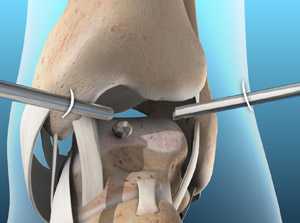

Как проходит операция в Геленк Клинике?

Артродез помогает восстановить безболезненность и потерянную подвижность. Данное вмешательство требует использования специальных винтов и интрамедуллярных гвоздей. Они фиксируют сустав до полной оссификации. © Gelenk-Klinik

Обездвиживание голеностопного сустава проводится под общим наркозом. Иногда используется и местная анестезия. Перед началом остеосинтеза, голеностоп освобождают от суставного хряща, то есть удаляют скользящий слой между суставными элементами голеностопа. Лишь после этой процедуры образуется прямой контакт между большеберцовой и таранной костями.

Прочное важное для остеосинтеза костное соединение, закрепляется при помощи винтов либо пластин. Артроскопические вмешательства подразумевают лишь микроскопические разрезы на коже. Сохранение мягких тканей является является важным элементов в таком лечении: только при низком рубцевании, в будущем возможно эндопротезирование.